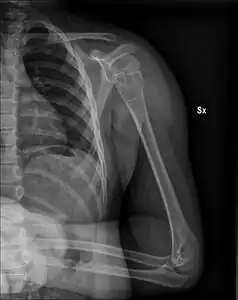

X-ray: Simple bone cyst in left upper arm of 13 year old

A simple bone cyst, also known as a solitary bone cyst, is a non-cancerous cavity in bone, filled with a yellow-colored fluid, usually in a long bone of a child.[1][2] It is usually discovered by chance as often there are no symptoms, but may present with an unexpected broken bone, pain, swelling or reduced movement.[1][2]

Most simple bone cysts do not cause any symptoms and are discovered as accidental findings on radiographs or CT scans made for other reasons.[3] Although it can form in any bone structure, it is predominantly found in the long bone of the upper arm near the shoulder, and long bone of the thigh near the hip.[6] Large lesions can cause nearby areas of bone to thin, which may result in a fracture and cause pain.[1][2] There may be a swelling or problem in moving the affected bone.[1]

Simple bone cysts are often found incidentally on X-rays. About 90 to 95% of the lesion is found in metaphysics of long bones. The cyst is centered, oblong in shape along the long axis of a long bone. Rarely, they are large and multicameral and are found in diaphysis. When fracture is present, there may be a small bone fragment migrated in the cystic fluid. This is called "fallen fragment sign" which is diagnostic of simple bone cyst. Besides, a bubble migrating upwards (known as "rising bubble sign") is another feature suggesting of simple bone cyst.[7]

Most simple bone cysts are diagnosed in growing bone in under 20 year olds.[1] Around half occur in the long bone of the upper arm and a quarter in the long bone of the thigh.[1] Males are twice as likely to be affected than females.[1]